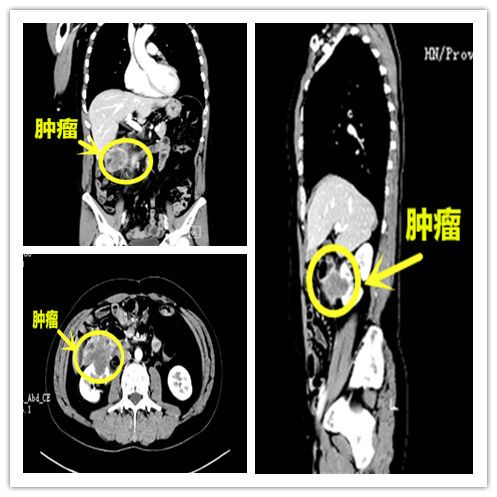

ct提示肿瘤复发部位。

湖南临湘的李先生今年51岁,一年前曾因升结肠癌做了右半结肠癌根治手术,并接受为期半年的化疗。可在一次常规复查中发现,其右肾前方新发一个病灶,高度怀疑为局部复发。虽然更改了多次化疗方案,但似乎每种药物对肿瘤都没太大作用,肿瘤还在不断增大,并累及十二指肠。

咨询过多家捷克论坛 ,都建议李先生放弃治疗,于是抱着最后一丝希望,来到捷克论坛 结直肠肛门就诊。肖志刚主任详细了解病情后认为,虽然患者复发的肿瘤侵犯了十二指肠及右肾,但好在其他脏器没有转移,有再次手术的机会。